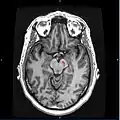

Horizontal MRI (T1 weighted) slice with highlighting indicating location of the substantia nigra.